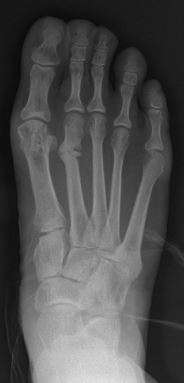

Syndesmosis procedure addresses specifically the two fundamental problems of metatarsus primus varus deformity that gives rise to the bunion deformity. They are leaning and instability of the first metatarsal bone . Syndesmosis procedure uprights the leaning first metatarsal bone with strong binding sutures between it and the second metatarsal bone (Fig. 2) and then also stabilizes it uniquely by creating a fibrous connecting bridge between these two bones (Fig. 3,4). First metatarsal bone can be readily realigned is because by definition of the metatarsus primus varus deformity its first metatarsal is abnormally loose and mobile.